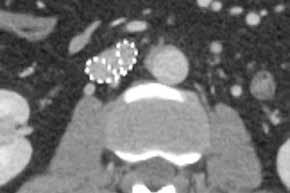

Metallartefaktreduktion serienmäßig

Mit SEMAR, der iterativen Metallartefaktreduzierung, können sogar schwierige Untersuchungen, z. B. mit Zahnfüllungen, Wirbelsäulenimplantaten, beidseitigen Hüftimplantaten, NeuroCoils und Schrittmachern durch einen flexiblen und reibungslosen Arbeitsablauf sicher ausgewertet werden. Der Single­Energy­Metall­Artefakt­Reduktionsalgorithmus beinhaltet zwei erfolgreiche Ansätze zur Reduzierung von Metallartefakten: Er kombiniert eine Strahlaufhärtungskorrektur mit dem Iterations­Hybridverfahren AIDR 3D Enhanced, um die Rauschtextur und scharfe Details neben Metallen wiederherzustellen. Dieser Prozess wird Schicht für Schicht über den gesamten Untersuchungsbereich durchgeführt, was in kürzester Zeit zu einem Artefaktfreien diagnostischen Bildstapel führt. SEMAR kann sowohl in schon hinterlegten, standardisierten Protokollen genutzt oder alternativ im Postprocessing über die Rohdaten ausgewählt und angewendet werden.

Die SEMAR-Metallartefaktreduktion minimiert die durch Implantate verursachten Bildstörungen und sichert so die Diagnostik sowohl des Metalls selbst wie auch des umliegenden Gewebes.